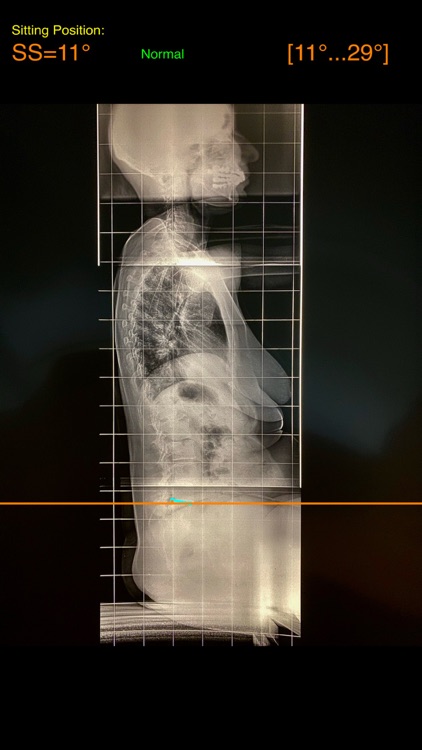

Evaluation of functional spinopelvic imaging in lateral radiographs in sitting and standing positions is of importance, especially in patient before total hip replacement surgery. Patients with concomitant hip and spine pathology undergoing primary total hip were identified as being at high risk for dislocation. Instability-prone patients arhtroplasty (THA) should appropriately assessed for the presence of deformity and abnormal spinopelvic mobility. The preoperative planning for THA should encompass evaluation of functional spinopelvic imaging in lateral radiographs in sitting and standing positions. Before planning cup position the surgeon should taken into account also anterior pelvic plane (APP) the coronal (functional) plane and the anterior pelvic plane tilt APPt or pelvic tilt and abnormal spinopelvic mechanics from standing to sitting.

The App is software aimed for orthopaedic surgeons, and allow to:

- mark certain points at the image of X-ray, and calculate at once the anterior pelvic plane tilt (APPt) or pelvic tilt , Pelvic incidence (PI), Sacral slope (SS), Lumbar lordosis (LL), Pelvic incidence Angle (PI) minus Lumbar lordosis Angle (LL)(PI–LL).

-According to measured parameters in standing and sitting lateral x- rays - based n a busy everyday practice, app offers a convenient way to perform radiographic measurements for spine, at the spinopelvic juncture - combing sitting and standing X-Rays, in a blink of an eye in front of your screen. The build in features of the app, allows results to be categorized and may help identify the complex “hip-spine” THA patient at high risk for postoperative instability and helps planning the optimum cup placement.